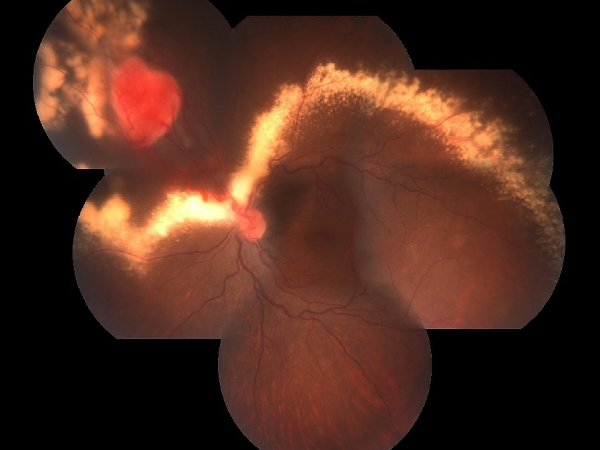

An untreated case of Diabetic Retinopathy with late diagnosis has become An Advanced Diabetic eye disease with Proliferative retinopathy, Preretinal and vitreous haemorrhage and Tractional retinal detachment. This stage requires a major vitreoretinal surgery with silicone oil tamponade and another procedure later on to remove the silicone oil